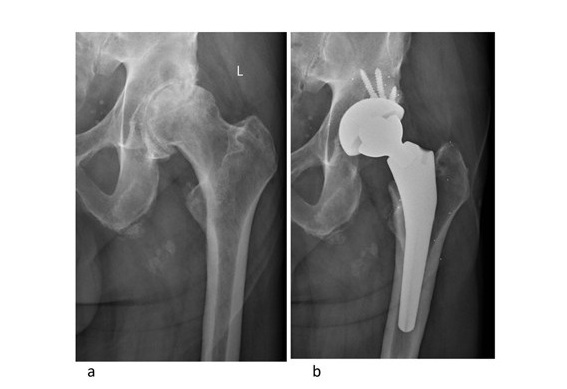

a) Pre- and b) postoperative radiographs of the Hip Innovation Technology Hip Replacement System implanted with radiostereometric analysis beads.

This novel reverse total hip arthroplasty (RTHA) design has been developed with enhanced mechanical stability at extremes of motion by reversing the articulating surfaces using a femoral cup and acetabular ball. The purpose of this study was to assess the implant-bone fixation using radiostereometric analysis (RSA), assess the linear wear of the cross-linked polyethylene insert and monitor the clinical safety and efficacy of this novel design.